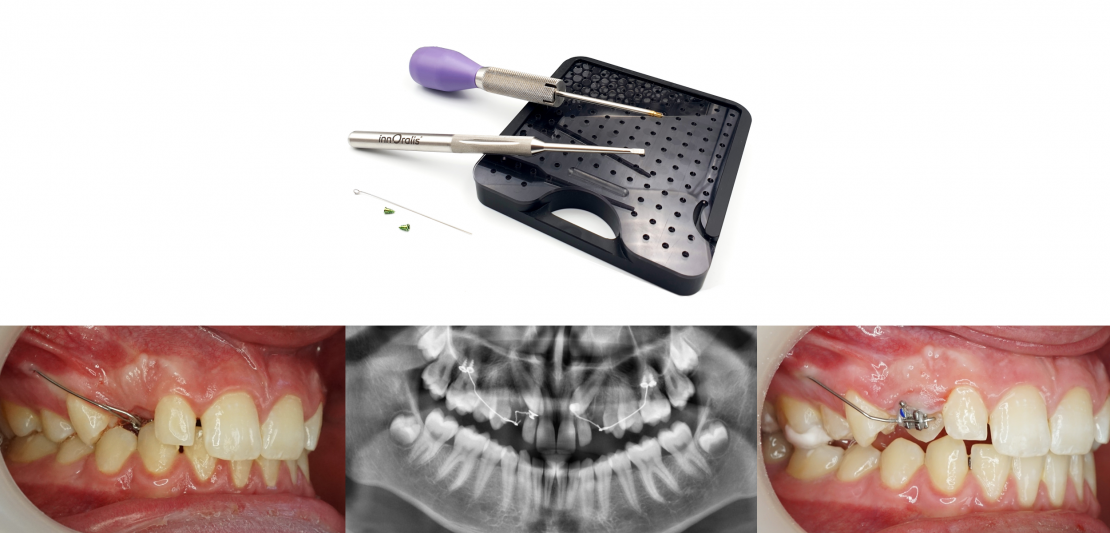

Les ancillaires CT8

Tournevis

- Il maintient à la fois la vis et sa connectique pour faciliter la mise en place

- Forme optimisée pour toutes les tailles de mains : le pommeau est parfaitement calé dans la paume et les doigts font tourner aisement le corps

- La connectique est libérable de son logement par une simple pression de l'index

Instrument à baïonnette

- Développé spécialement pour le Système CT8, il permet de réaliser le pli d'émergence de la connectique, appelée baïonnette, au niveau du trait d'incision d'un seul mouvement

- La forme de la fente ont en effet été optimisés afin de réaliser aisément ce pliage

Rack de rangement et stérilisation

- Conçu spécialement pour contenir le Système CT8, il est compatible avec la stérilisation par autoclave vapeur

- Des logements individuels par kits facilitent le repérage et l'identification d'un lot pour une meilleure traçabilité

- Fixation de la vis et de la connectique sur le tournevis

La vis est fixée sur le tournevis en la prenant avec pression sur le rack et en exerçant un léger mouvement de rotation avec le tournevis. Puis elle est enfilée dans la boucle de la connectique.

L’extrémité du bras de la connectique est ensuite bloquée dans la fente du tournevis (excepté pour le CT8-2 tunnel qui est placé manuellement, indépendamment du tournevis).

S’il y a deux boucles, la vis est enfilée dans celle qui sera la plus mésiale (ou la plus occlusale dans le cas d’un CT8-1 longitudinal).